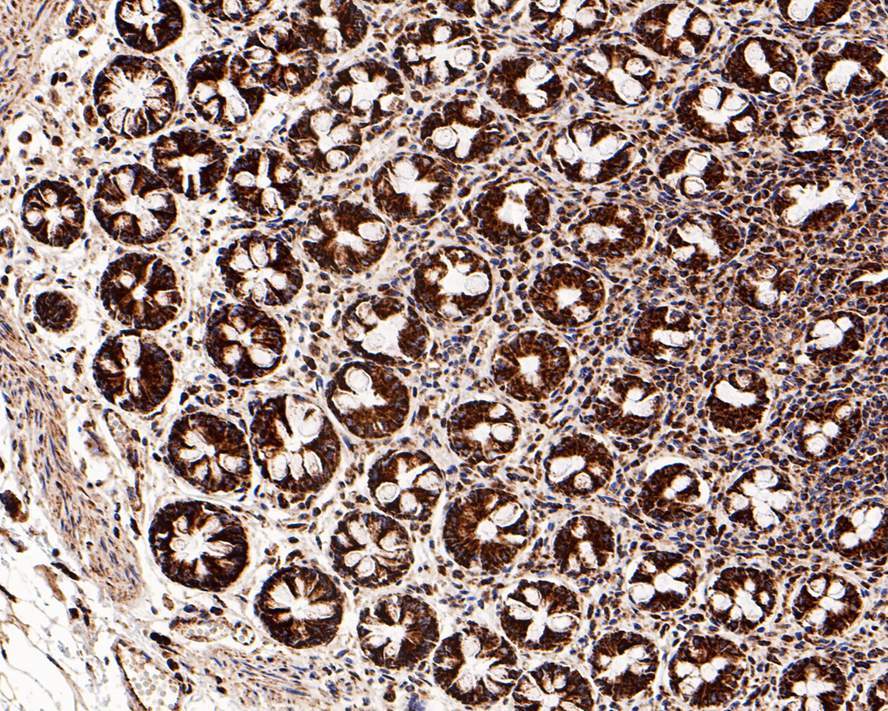

- Submitted by

- Invitrogen Antibodies (provider)

- Main image

- Experimental details

- Immunohistochemistry analysis of GC1q R in paraffin-embedded human large intestine tissue. The section was pre-treated using heat mediated antigen retrieval with Tris-EDTA buffer (pH 9.0) for 20 minutes. The tissues were blocked in 1% BSA for 20 minutes at room temperature, washed with ddH2O and PBS, and then probed with GC1q R Monoclonal antibody (Product # MA5-44926) using a dilution of 1:1,200 for 1 hour at room temperature. The detection was performed using an HRP conjugated compact polymer system. DAB was used as the chromogen. Tissues were counterstained with hematoxylin and mounted with DPX.